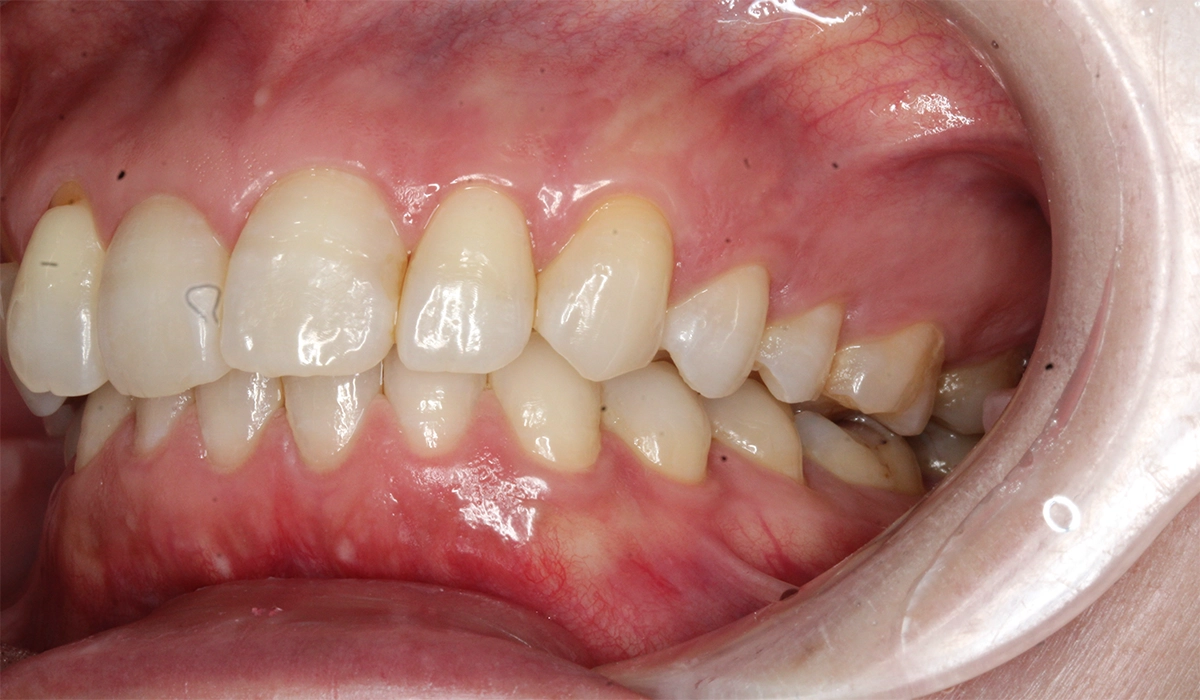

術前:右側